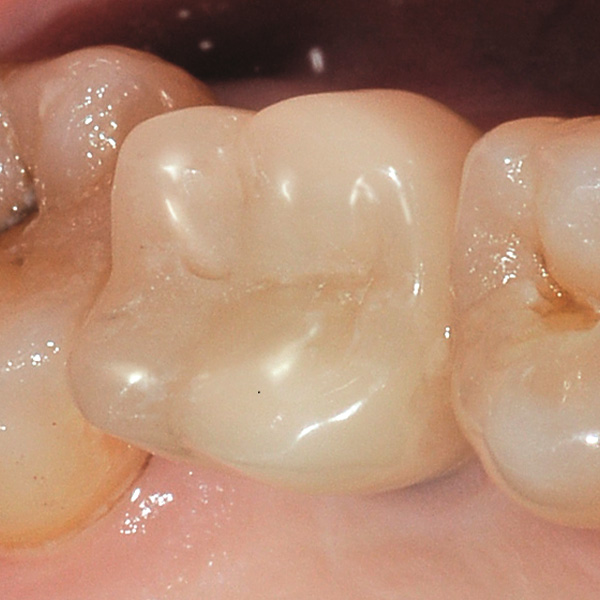

Restauri supportati da impianti sono soggetti a carichi particolarmente elevati. Dopo l‘estrazione e l‘impianto al paziente manca l‘apparato di fibre elastiche del letto dentale naturale. Per questo motivo le forze di masticazione non vengono assorbite, ma trasmesse direttamente sul restauro, l‘impianto, l‘osso e la dentatura antagonista. La ceramica ibrida VITA ENAMIC ha una struttura a reticolo duale in ceramica (86 % in peso) e polimero (14 in peso). Ne risulta un‘elasticità simile alla dentina e la capacità do assorbire le forze di masticazione. Il blocchetto policromo VITA ENAMIC multiColor in geometria EMC-16, grazie alla sua elevata dimensione verticale, consente di realizzare corone-abutment monoblocco, monolitiche anche nel caso di osso atrofizzato. L‘odontoiatra Professor Dr. Alexander Hassel mostra in questo contributo come riabilita una paziente con questa forma di restauro.